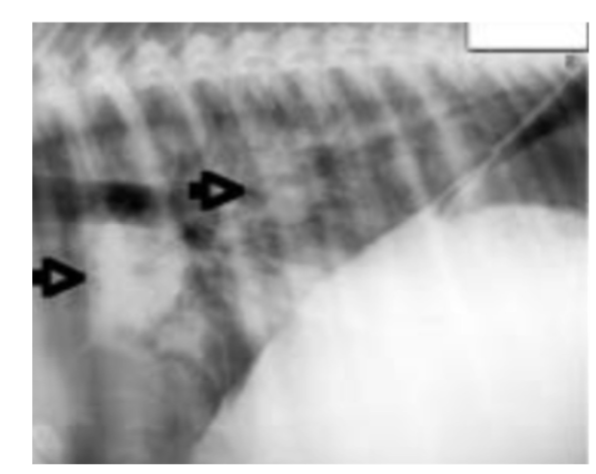

• what pattern is seen in this image?

bronchoalveolar